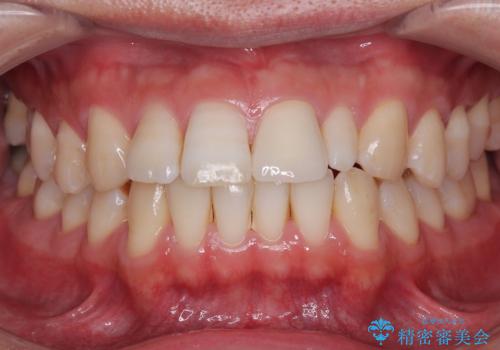

- 隙間を埋めた材料の変色や形を気にして来院された患者様です。

矯正治療などを含めて治療方法を相談した結果、当該歯をオールセラミッククラウンにて補綴治療を行うこととしました。

前歯の単独歯の補綴治療であったので、オーダーメイドタイプをおすすめしましたが、今回は既製タイプにて製作を進めました。

既製タイプでしたが、違和感のない仕上がりとなりました。